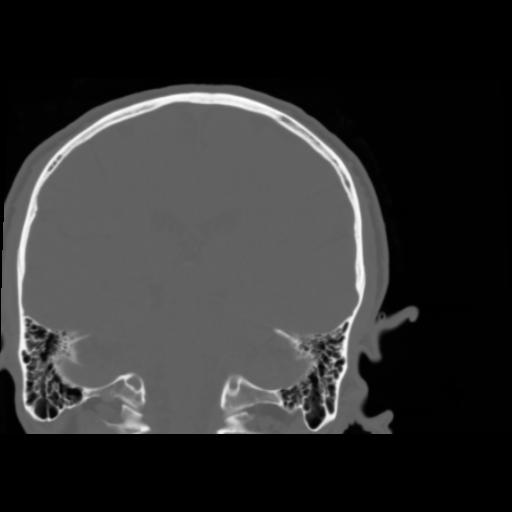

5 CEREBRO,,Coronal,3.000,CEREBRO,Coronal,